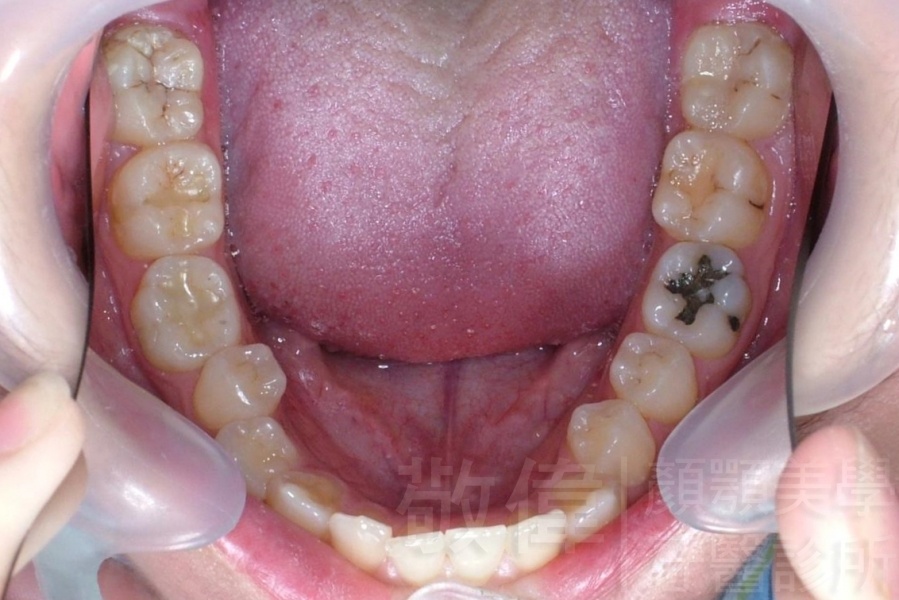

齒顏矯正/上顎暴牙且牙齒極度混亂

矯正前-右   矯正前-正   矯正前-左

矯正前-上   矯正前-下

<個案說明>

上顎暴牙且牙齒極度混亂,經由矯正之後,臉型大幅度改善,牙齒的排列更加的整齊健康。相較於之前眼神充滿精神,自信心展現無遺。